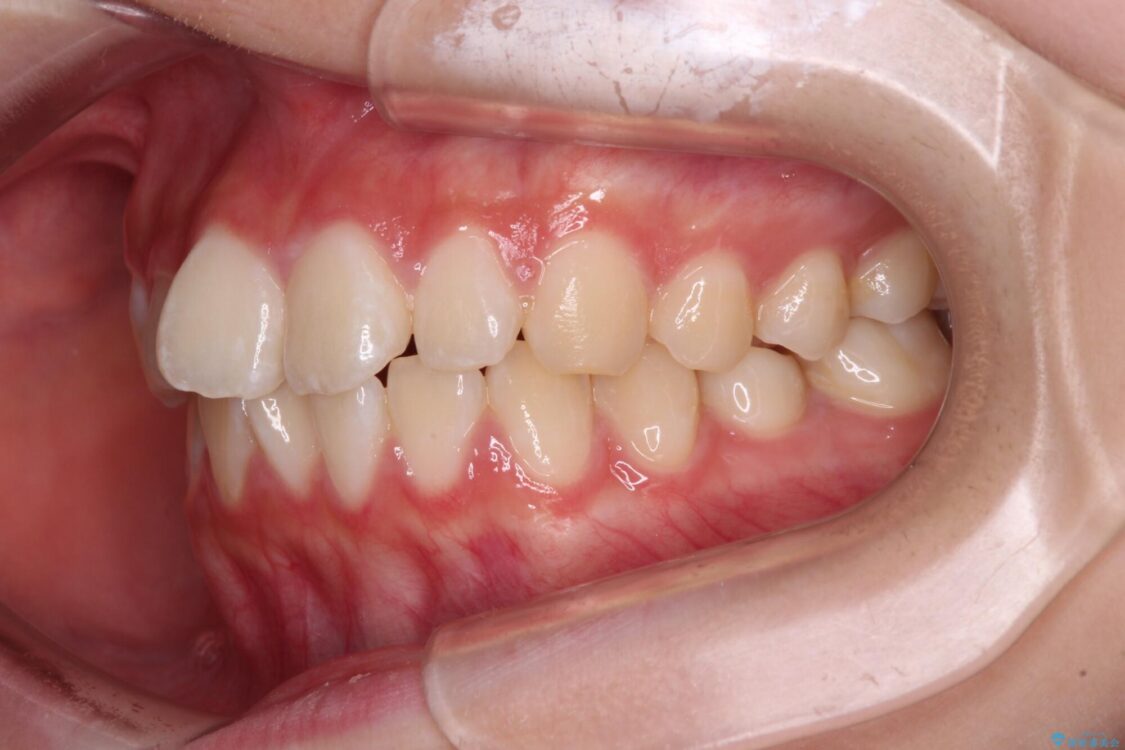

治療前

• インビザラインは使える自信がない ワイヤー装置にて矯正治療 治療前画像